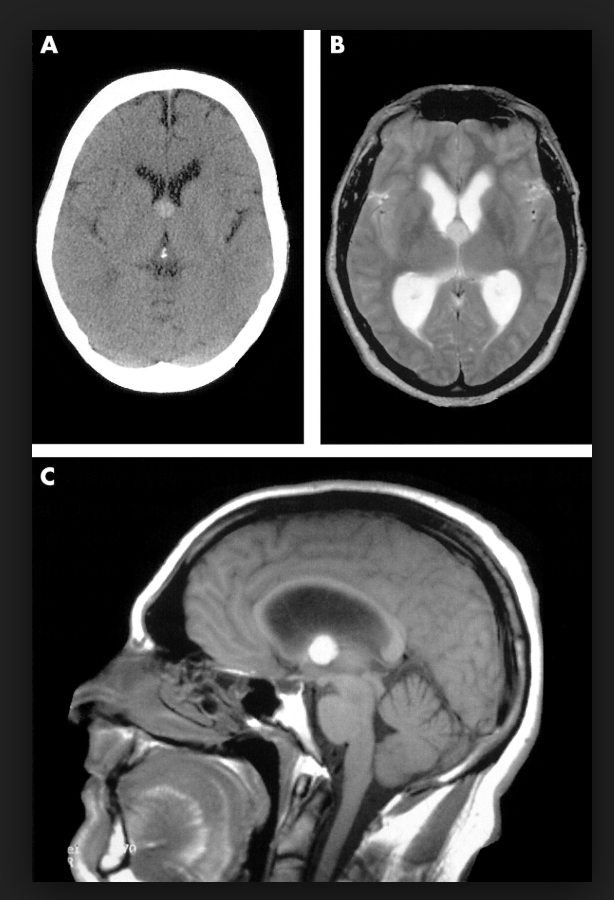

图1

图1 脑内皮样囊肿